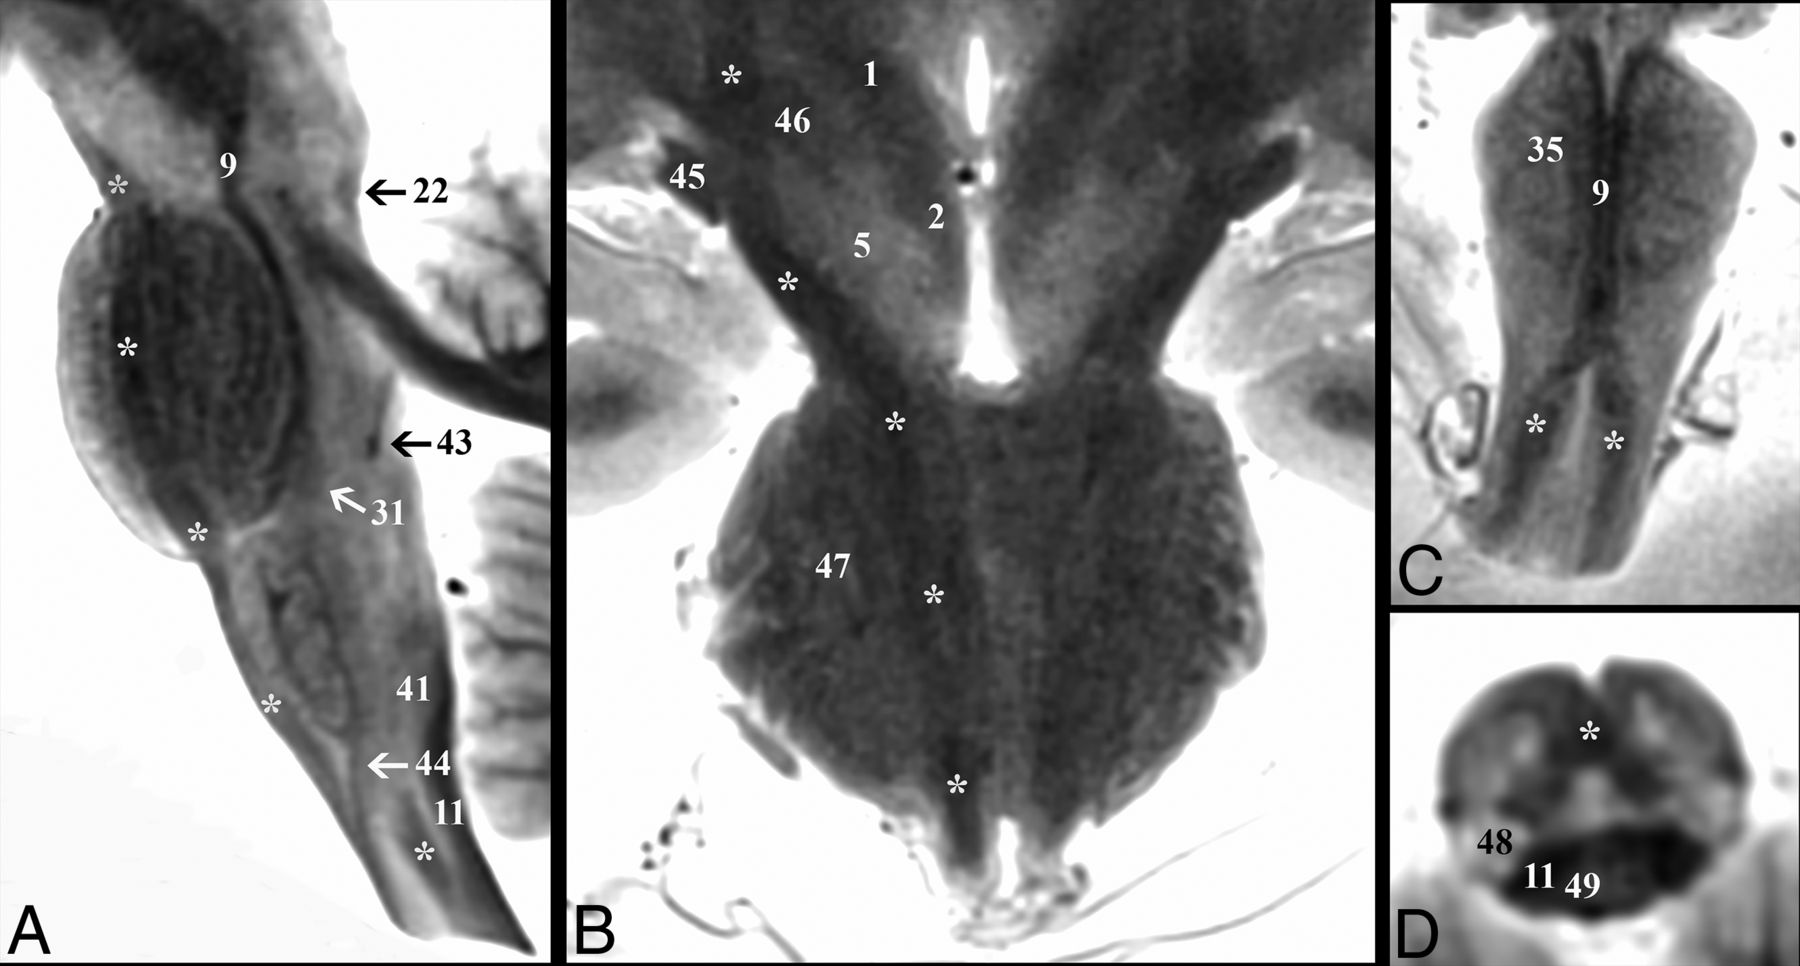

Parasagittal and coronal T2-weighted MR images of the postmortem human brain stem. A, Canonical axial brain stem levels parallel to the anterior/posterior commissure plane that are found in Fig 2 are represented with the solid lines and On-line Fig 1 with the dashed line. Only selected brain stem substructures are labeled in coaligned sagittal and coronal images to orient the reader relative to the craniocaudal axial slice positions. The On-line Table provides a complete list of labeled anatomy for all figures, indicated by the numbers in parentheses in the legends. Note the trochlear nerve (asterisk, C) only seen in some brains.

Demonstration of the corticospinal tract (asterisk) throughout the brain stem. A, Parasagittal image depicts the corticospinal tract descending within the brain stem from the cerebral peduncle to the upper cervical cord. B, Coronal image shows the course of the corticospinal tract from the posterior limb of the internal capsule to the most superior aspect of the medullary pyramids. Note in the diencephalic junction, the close relationship of the corticospinal tract to the optic tract (45) laterally and the subthalamic nucleus (46) medially. Oblique coronal (C) and oblique axial (D) images highlight the decussation of the corticospinal tracts at the cervicomedullary junction. C, The paramedian dark lines are the medial lemniscus (9), which is superficial to the corticospinal tract on this oblique axial image.